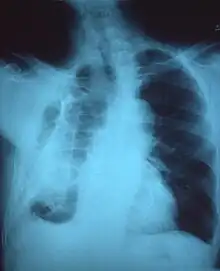

| Fibrothorax on chest x-ray | |

A fibrothorax can typically be diagnosed by taking an appropriate medical history in combination with the use of appropriate imaging techniques such as a plain chest X-ray or CT scan.[3] These imaging techniques can detect fibrothorax and pleural thickening that surround the lungs.[7] The presence of a thickened peel with or without calcification are common features of fibrothorax when imaged.[3] CT scans can more readily differentiate whether pleural thickening is due to extra fat deposition or true pleural thickening than X-rays.[3]

If a fibrothorax is severe, the thickening may restrict the lung on the affected side causing a loss of lung volume.[7] Additionally, the mediastinum may be physically shifted toward the affected side.[3] A reduction in the size of one side of the chest (hemithorax) on an X-ray or CT scan of the chest suggests chronic scarring.[6] Signs of the underlying disease causing the fibrothorax are also occasionally seen on the X-ray.[6] A CT scan may show features similar to those seen on a plain X-ray.[7] Lung function testing typically demonstrates findings consistent with restrictive lung disease.[6]

Extensive left-sided fibrothorax

Chest radiograph displaying inhomogeneous opacification of the left half of the chest that is fibrothorax